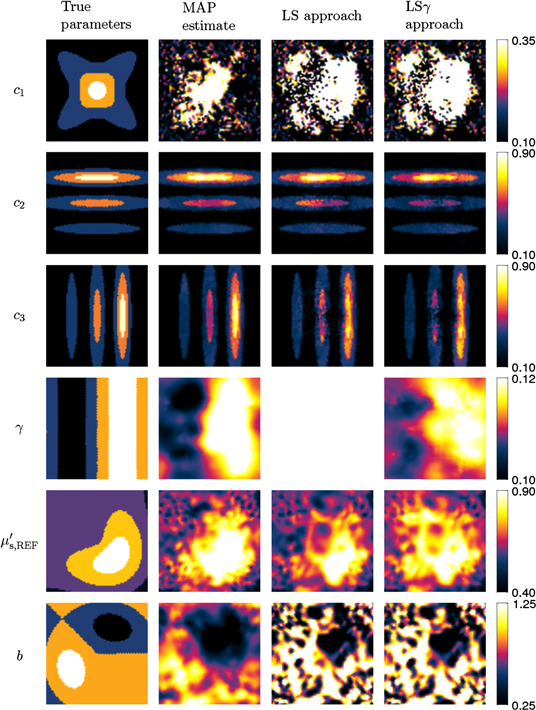

, γ,  and b used to simulate the data in the two cases are presented in the first columns of figures 1 and 2 for the smoothly and sharply varying parameter cases respectively.

and b used to simulate the data in the two cases are presented in the first columns of figures 1 and 2 for the smoothly and sharply varying parameter cases respectively.  was defined at a reference wavelength

Figure 1. True and reconstructed chromophore concentrations  ,

,  ,

,  , Grüneisen parameter γ, and scattering parameters

, Grüneisen parameter γ, and scattering parameters  and b for the case of smoothly varying material parameters. First column shows the true parameters. Second column shows the MAP estimates. Third and fourth columns show the estimates using the LS and LSγ approaches respectively.

and b for the case of smoothly varying material parameters. First column shows the true parameters. Second column shows the MAP estimates. Third and fourth columns show the estimates using the LS and LSγ approaches respectively.

Standard image High-resolution imageFigure 2. True and reconstructed chromophore concentrations  ,

,  ,

,  , Grüneisen parameter γ, and scattering parameters

, Grüneisen parameter γ, and scattering parameters  and b for the case of sharply varying material parameters. First column shows the true parameters. Second column shows the MAP estimates. Third and fourth columns show the estimates using the LS and LSγ approaches respectively.

and b for the case of sharply varying material parameters. First column shows the true parameters. Second column shows the MAP estimates. Third and fourth columns show the estimates using the LS and LSγ approaches respectively.

The second column of figure 2 shows MAP estimates in the case of sharply varying spectral parameters. The reconstructions are similar to the case of smoothly varying spectral parameters. Estimates of  and

and  show the sharp changes in the true parameters. However, the estimates of

show the sharp changes in the true parameters. However, the estimates of  , γ,

, γ,  and b do not show the sharp changes, while the overall shape of the estimates are similar to the true parameters.

and b do not show the sharp changes, while the overall shape of the estimates are similar to the true parameters.

The third column of figure 1 shows the estimates of the spectral properties of the target for the LS approach (known γ) for the smoothly varying parameter case. It is observed that the estimates of  and b do not resemble the true parameter distributions, while the estimates of

and b do not resemble the true parameter distributions, while the estimates of  ,

,  and

and  do. Similar behaviour is observed in the case of sharply varying material parameters shown in the third column of figure 2.

do. Similar behaviour is observed in the case of sharply varying material parameters shown in the third column of figure 2.

The fourth column of figure 1 shows the estimated spectral parameters of the target for the LSγ approach (unknown γ) for the smoothly varying parameter case. The estimates of  and

and  seem to resemble the true parameters. It is oberserved that the estimate of γ is not very good and that the estimate of

seem to resemble the true parameters. It is oberserved that the estimate of γ is not very good and that the estimate of  is worse than in the LS approach. As in the LS approach, the estimate of b using the LSγ does not resemble the true parameter distribution. The fourth column of figure 2 shows the estimates for the sharply varying material parameter case. In this case

is worse than in the LS approach. As in the LS approach, the estimate of b using the LSγ does not resemble the true parameter distribution. The fourth column of figure 2 shows the estimates for the sharply varying material parameter case. In this case  resembles the true parameter distribution even less than in the case of smoothly varying material parameters. Otherwise the estimates behave as in the case of the smooth material parameters.

resembles the true parameter distribution even less than in the case of smoothly varying material parameters. Otherwise the estimates behave as in the case of the smooth material parameters.